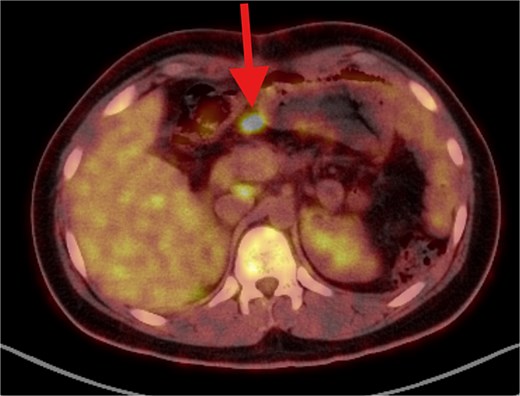

The patient underwent left lateral hepatectomy and cholecystectomy following diagnosis. Histopathology confirmed undifferentiated embryonal sarcoma (UES) of the liver with a 1 mm clear margin (Fig. 1); immunohistochemistry supported the diagnosis. The gallbladder showed chronic cholecystitis, and the lymph nodes were tumor-free. Postoperative imaging after two months revealed a recurrent mass near the stomach (Fig. 2), confirmed as recurrent UES by biopsy. Re-excision showed extensive necrosis and peritoneal infiltration. Positron emission tomography – computed tomography (PET-CT) later identified peritoneal and mesenteric metastases (Fig. 3). Follow-up PET-CT also revealed multiple small hypermetabolic hepatic nodules in addition to peritoneal and mesenteric lesions, indicating intrahepatic disease recurrence. Six cycles of chemotherapy resulted in near-complete resolution of metabolic lesions, with minimal residual activity. Follow-up imaging showed near-complete resolution of hepatic nodules, with only one residual, non-suspicious tiny nodule. After additional chemotherapy and targeted therapy cycles, PET-CT revealed new focal hypermetabolic activity near the splenic flexure, anterior to the spleen, raising concern for recurrence (Fig. 4). The patient underwent omentectomy and splenectomy. Histopathology confirmed metastatic UES in a 2.5 cm splenic lesion with hemorrhage and necrosis, and a 0.4 cm omental nodule, both completely excised. A total of 15 chemotherapy cycles were completed. Post-treatment imaging showed a mixed-density lesion in the splenic bed with FDG uptake, possibly post-surgical, and a new hypermetabolic mesenteric nodule (Fig. 5). Magnetic resonance imaging showed a cystic post-surgical collection without enhancing lesions. Subsequent imaging revealed regression of the splenic bed lesion and resolution of the mesenteric nodule; however, a new hypermetabolic mesenteric density emerged (Fig. 6). The lesion was placed under active surveillance, with additional chemotherapy administered and repeat imaging scheduled to assess response. Bilateral axillary lymph nodes showed reactive hypermetabolism. The patient, having undergone hepatectomy, splenectomy, and multimodal therapy, remains under close surveillance with encouraging treatment response.

PET/CT scan showing a clear surgical bed. Almost complete metabolic resolution of the previous hypermetabolic abdominal deposits. Development of focal hypermetabolic activity just anterior and abutting the lower spleen pole, at the projection of splenic flexure of the descending colon, this lesion is nonspecific.